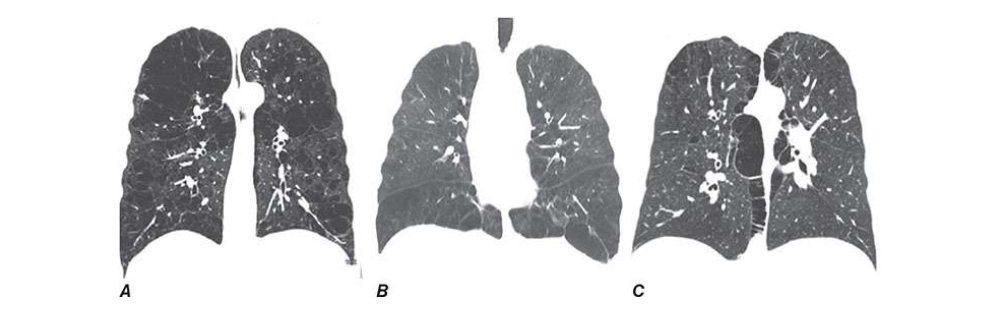

Radiographic studies may assist in the classification of the type of COPD. Obvious bullae, paucity of parenchymal markings, or hyperlucency suggests the presence of emphysema. Increased lung volumes and flattening of the diaphragm suggest hyperinflation but do not provide information about chronicity of the changes. Computed tomography (CT) scan is the current definitive test for establishing the presence or absence of emphysema in living subjects (Fig. G-4) and (Fig. G-5). From a practical perspective, the CT scan does little to influence therapy of COPD except in those individuals considering surgical therapy for their disease (described below).

severe upper lobe involvement in a 68-year-old man with a 70-pack-year smoking

history but forced expiratory volume in 1 s (FEV1) 81% predicted (GOLD

spirometry grade 1). B. Panlobular emphysema with diffuse loss of lung

parenchymal detail predominantly in the lower lobes in a 64-year-old man with

severe α1 antitrypsin (α1AT) deficiency. C. Paraseptal emphysema with marked

airway inflammation in a 52-year-old woman with a 37-pack-year smoking history

and FEV1 40% predicted.